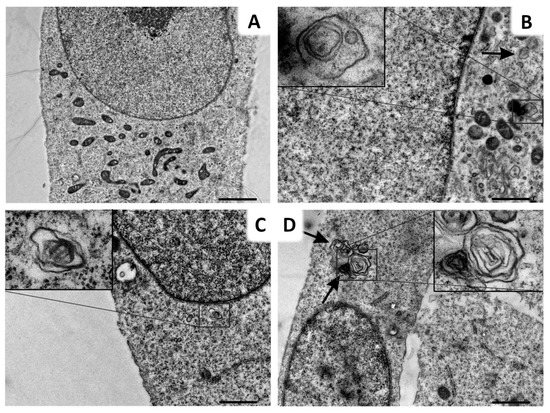

2.5. Lys05 Induces the Early-Stage Autophagy but Subsequently Leads to Its Inhibition Resulting in Lysosome Accumulation

2.6. Lys05 Potentiates Autophagy Inhibition in H1299 Cells via Accumulation of Autophagosomes